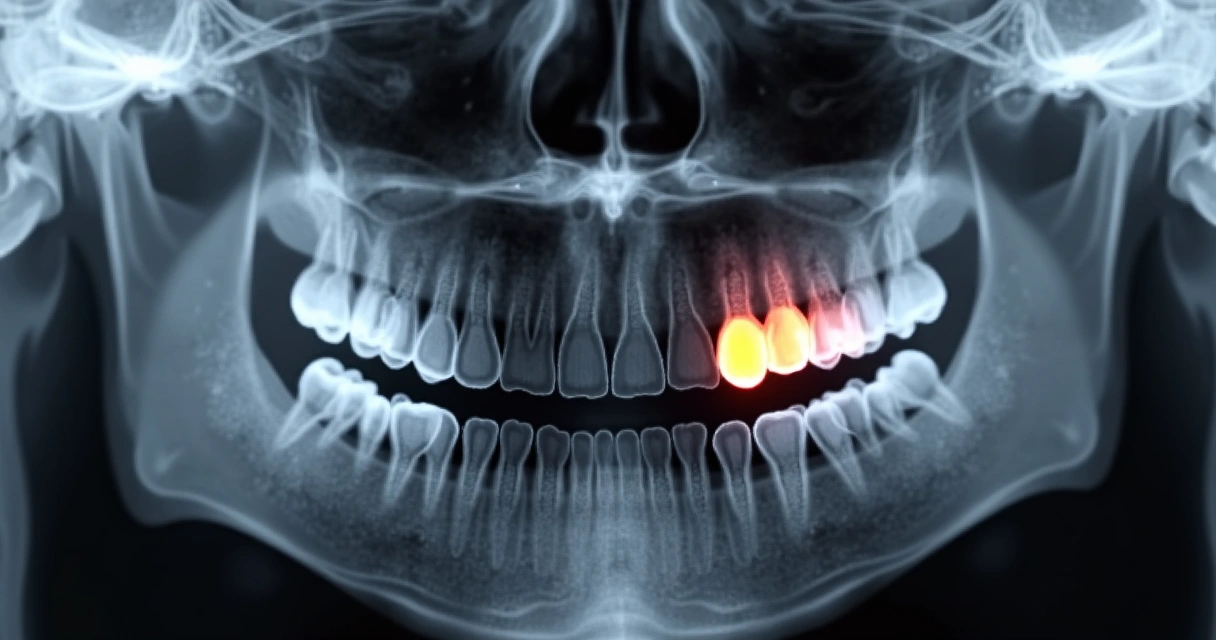

- Radiografias panorâmicas podem detectar infecções silenciosas antes que causem danos sistêmicos.

Um detalhe essencial, muitas vezes negligenciado, é a realização de radiografias panorâmicas a cada visita odontológica. Eu costumo explicar aos meus pacientes que esse exame de imagem possibilita a visualização de áreas problemáticas que não aparecem a olho nu. Por meio da radiografia, conseguimos identificar cistos, abscessos ocultos e até mesmo alterações ósseas, antes de produzirem sintomas visíveis.